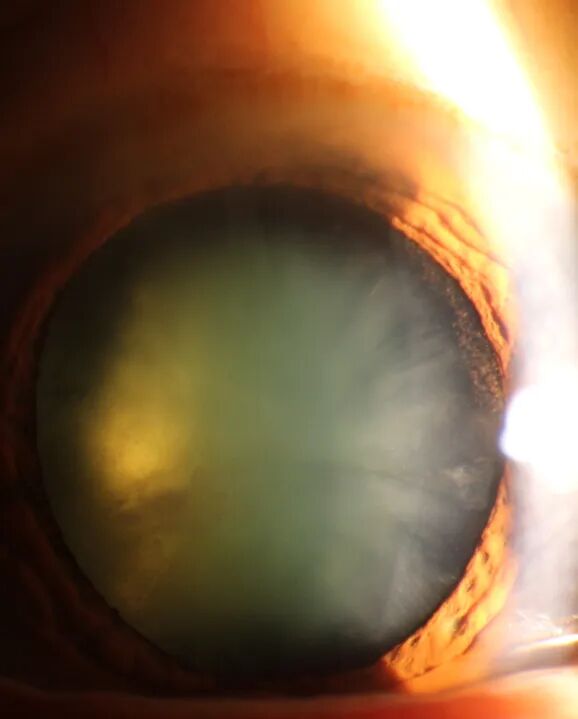

09            白内障

由于先天性因素、衰老、外伤、炎症、药物中毒等因素,破坏晶状体的组织结构,干扰其正常代谢而使晶状体浑浊形成白内障(左)。若白内障术后残留的晶状体上皮细胞发生增殖、迁移、纤维化,还将会形成后发障(右)。